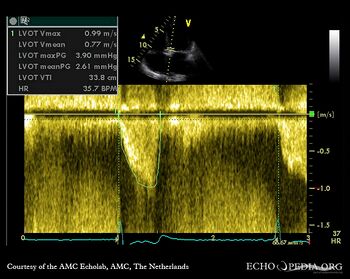

| Pulsed-wave Doppler signal: LVOT flow